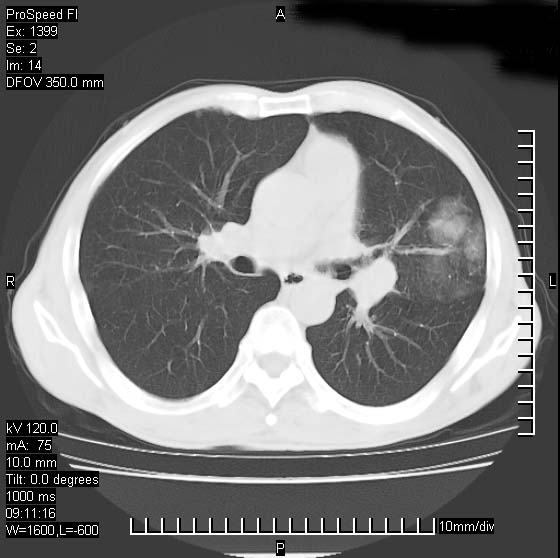

以下是引用卜一在2007-1-19 9:55:00的发言:[br]左肺沿胸膜下巨大肿块影,边缘呈分叶征,纵隔内见肿大淋巴结,右肺内另见一不规则结节影 .考虑:左肺周围性肺癌伴纵隔 右肺内转移.

以下是引用rgsyyf在2007-1-19 11:05:00的发言:[br]左肺上叶见形态不规则巨大软组织肿块影,边缘呈分叶征,纵隔内隆突下见肿大淋巴结,右肺内另见一不规则结节影 .考虑:左肺周围性肺癌伴纵隔即右肺内转移.